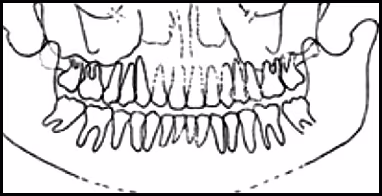

These figures demonstrate the visual effects on the image when the patient’s head is too far forward during exposure: spine superimposes over the ramus area, nasal fossa and maxillary sinus become clearly evident, and the anterior teeth are narrowed and blurred.

Figure 51A. Panoramic Image.

Figure 51B. Panoramic Schematic.